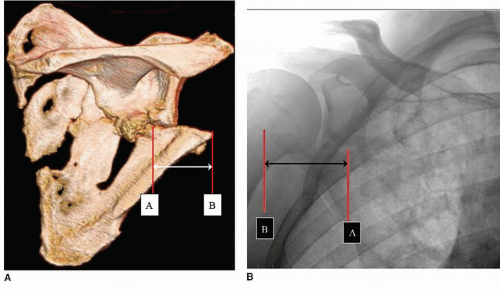

The structural anatomy of the clavicle dictates both its fracture patterns and the surgical approaches utilized for fixation. The medial two-thirds are convex anteriorly and tubular in cross-section, while the lateral one-third is concave anteriorly and flattened superior-inferiorly. The midshaft is the narrowest and weakest portion, lacking ligamentous support, making it most susceptible to fracture under axial loading.

Muscular attachments exert significant deforming forces on fracture fragments. Superiorly, the trapezius inserts on the lateral third, while the sternocleidomastoid originates from the medial third. Inferiorly, the subclavius lies in the subclavian groove, the pectoralis major originates from the medial half, and the deltoid originates from the lateral half. Ligamentous attachments include the sternoclavicular ligaments medially and the acromioclavicular and coracoclavicular ligaments laterally. The coracoclavicular ligaments (trapezoid and conoid) are crucial for suspending the scapula from the clavicle.

Biomechanics of Fracture and Displacement

Midshaft clavicle fractures typically result in characteristic displacement patterns driven by the aforementioned muscular attachments. The medial fragment is invariably pulled superiorly and posteriorly by the sternocleidomastoid muscle. Conversely, the lateral fragment is pulled inferiorly and medially by the weight of the arm and the action of the deltoid and pectoralis major muscles.

This combination of forces frequently leads to significant shortening, particularly in the presence of comminution. Shortening greater than 1.5 to 2.0 centimeters alters the resting length and tension of the shoulder girdle musculature, altering glenohumeral and scapulothoracic kinematics. Biomechanical studies have demonstrated that significant clavicular shortening decreases the efficiency of the pectoralis major and latissimus dorsi, and can lead to scapular dyskinesia. The intramedullary canal of the clavicle is relatively narrow and variable, making traditional intramedullary nailing technically demanding and less rotationally stable for comminuted patterns compared to plate osteosynthesis.